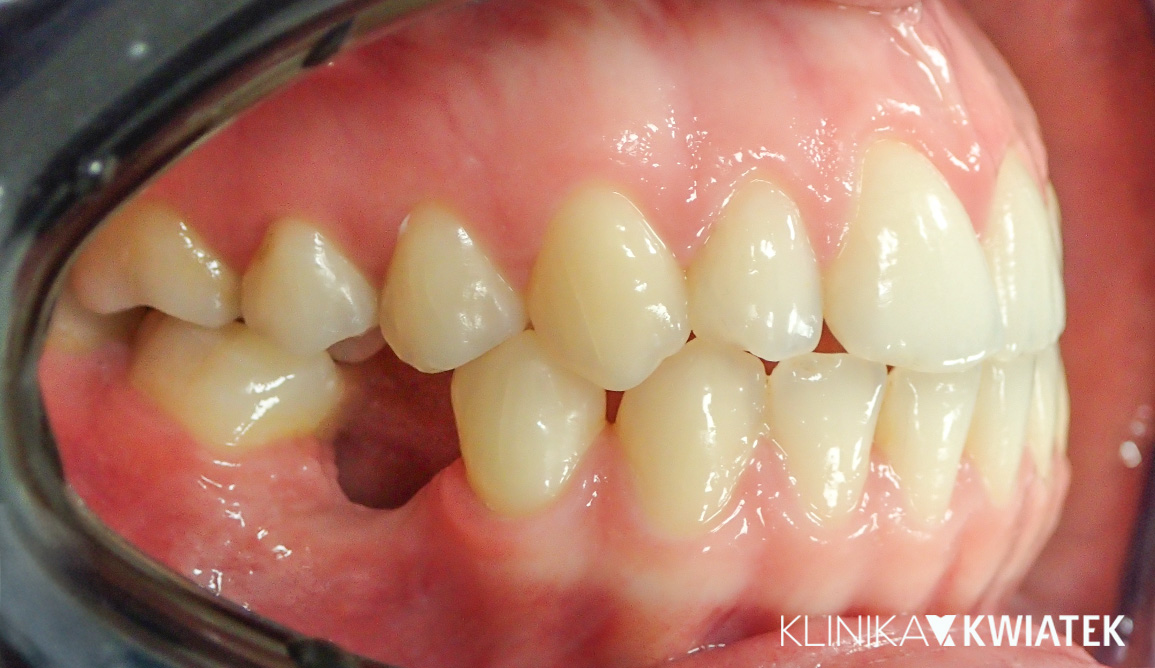

Zatrzymany kieł? Nowoczesna ortodoncja ma rozwiązanie!

27 letnia Pacjentka zgłosiła się do naszej kliniki z problemem wyrzynającego się nieprawidłowo kła górnego, przesuniętą linią pośrodkową i powiększonym nagryzem pionowym. Dzięki kompleksowej diagnostyce, leczeniu ortodontycznemu z zastosowaniem aparatów estetycznych i metalowych, wsparciu fizjoterapeutycznemu oraz regularnym higienizacjom udało się uzyskać prawidłową funkcję i estetykę uśmiechu. Efektem końcowym jest harmonijny zgryz, stabilne utrzymanie rezultatów dzięki retencji oraz piękny, zdrowy uśmiech.